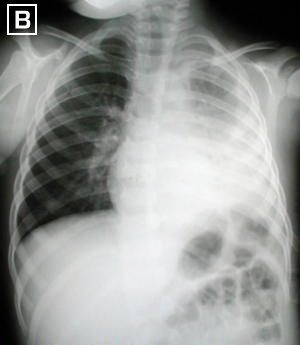

Rx. Tórax PA.(B). Disminución de los espacios intercostales izquierdos, engrosamiento pleural severo , borramiento de los senos costo-frénicos, elevación hemi-diafragma izquierdo.escoliosis dorsal leve y poco aclaramiento del vertice por fibrosis pleural y atelectasia pulmonar.

• Debo recordar que la decorticación en fase temprana ( Rx Torax PA (B) ), al iniciar el control de la infección es recomendada por facilitar la recuperación temprana, logra el control total del proceso inflamatorio, disminuye el tiempo de hospitalización, evita la recidiva del proceso neumonico y de otras complicaciones, además que el procedimiento de decorticación es técnicamente mas sencillo, menos cruento, al ser mas laxas las adherencias fibroticas y se evitan las deformidades por la retracción de la fibrosis.